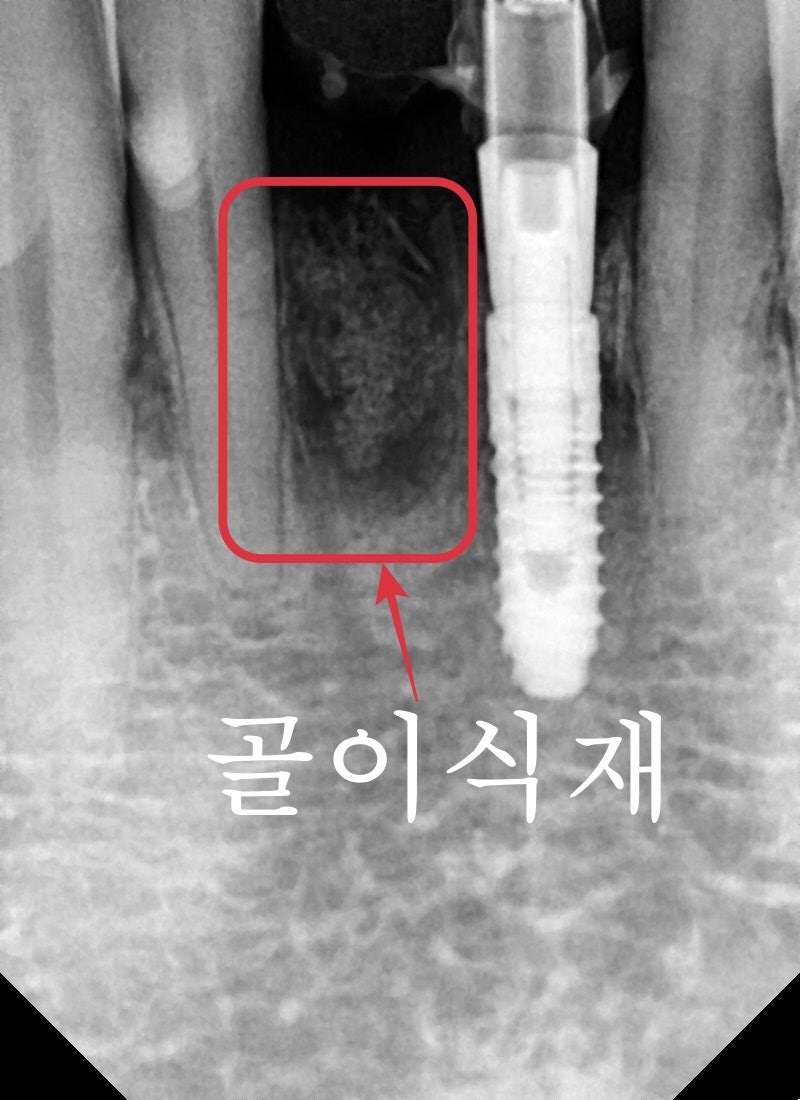

2개의 치아가 치주염으로 인한 치조골 소실로

2개의 치아 중 한 개는 치주염이 상당히 많이 진행되어 있었고, 그 옆 치아도 2도 이상의 동요도가 관찰되어 2개의 치아가 발치가 필요했습니다.

수술은 치주염이 심해 치조골이 많이 흡수된 곳은

치조골 이식술을 통해 잇몸 볼륨을 유지시켜

시간이 지나도 잇몸이 꺼지지 않도록 유지시켜주고

임시 기둥을 통해 임시치아를 제작했습니다.